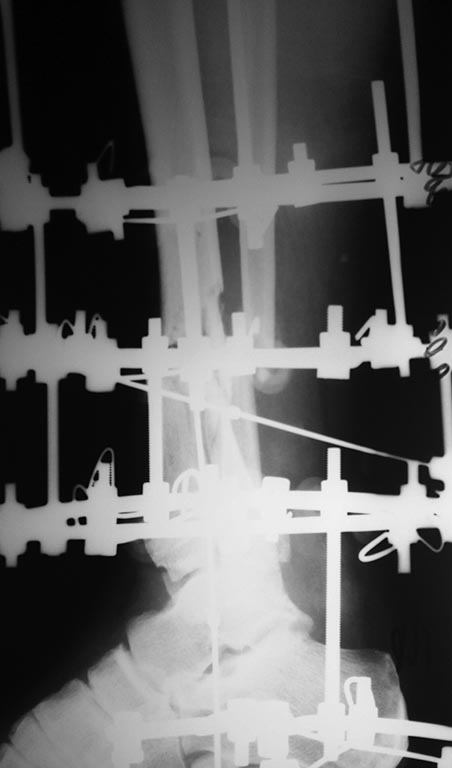

Небольшое уточнение: оперирован 1 августа, в ноябре снята база со стопы,

в конце декабря демонтаж аппарата. Показания к снятию аппарата-

заключение рентгенолога - консолидирующийся перелом, отсутствие

патологической подвижности. Рана заживала около 3 -х месяцев условно

первичным натяжением. Так как нет КТ руководствовались в основном

рентген снимками.

Снимки при поступлении, спустя 2,5 месяца. Рентген снимки после снятия

аппарата в архиве пришлю позже. Осылаю КТ от апреля.